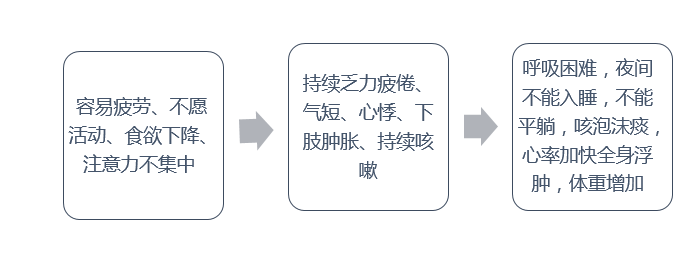

三、哪些症状是心衰信号?

♥1.如果您是心脏病或高血压患者,在过度劳累或者情绪波动以后,出现了呼吸困难、不能平躺、心悸、下肢水肿等表现,应该及早到心血管专科就诊

♥2.如果您不知道既往有没有心脏病史,突然感到喘不上气、心慌、特别疲乏、甚至脚踝、腿出现水肿,应该尽快就医,排除心衰的可能

♥3.如果以往的心电图或心脏超声出现过异常,当时未诊断为心衰,而后来出现了气喘、呼吸困难、疲劳乏力的表现,应该及时到医院心脏专科就诊